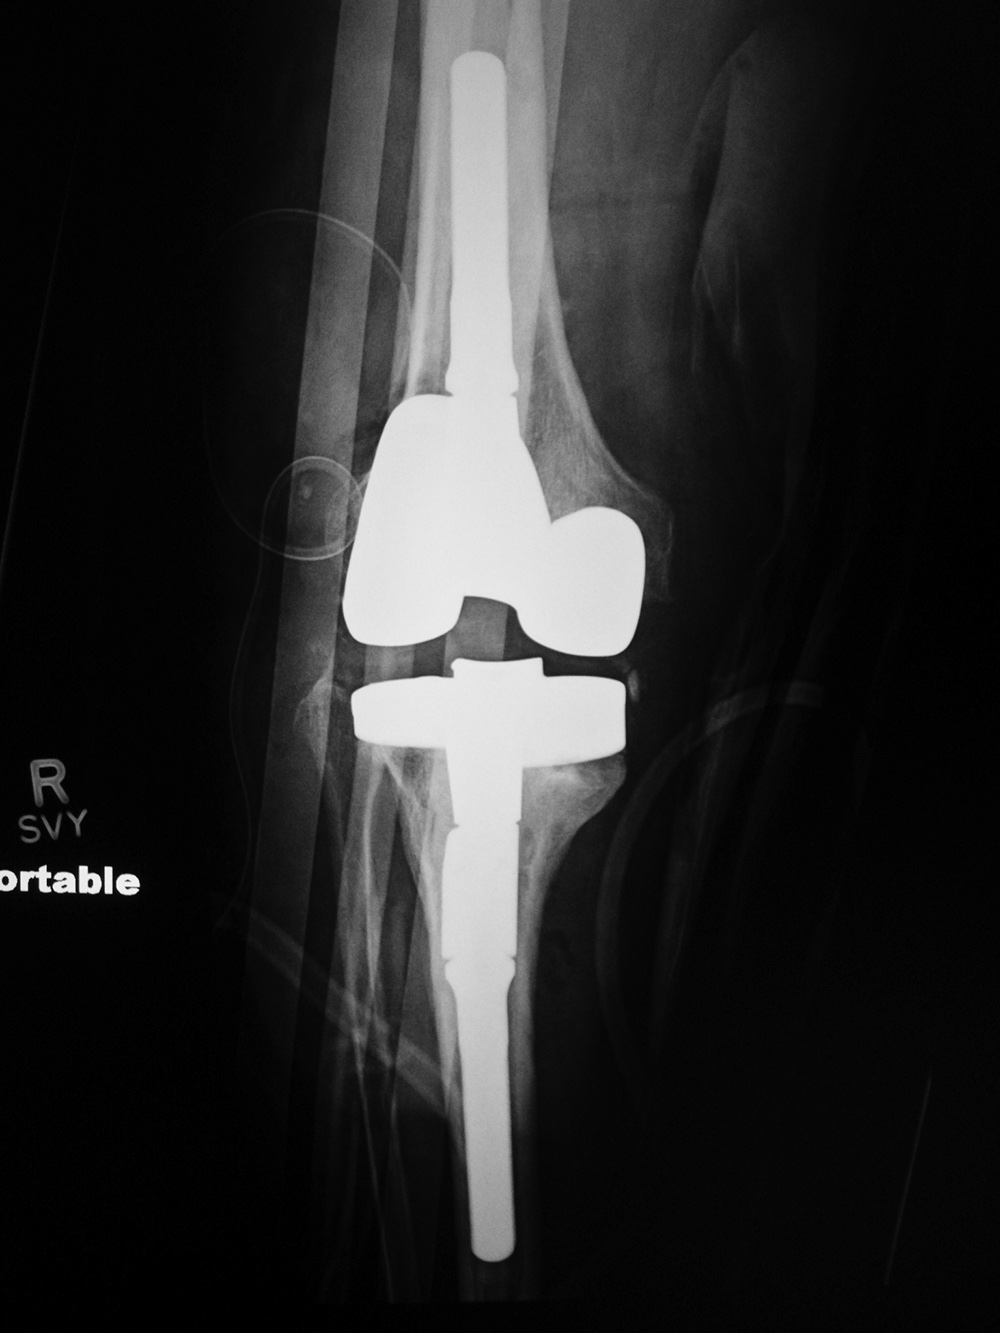

| 68 year-old woman treated for severe left knee osteoarthritis |

Note the large distal femoral box. There is a surgical drain in the suprapatellar space. |